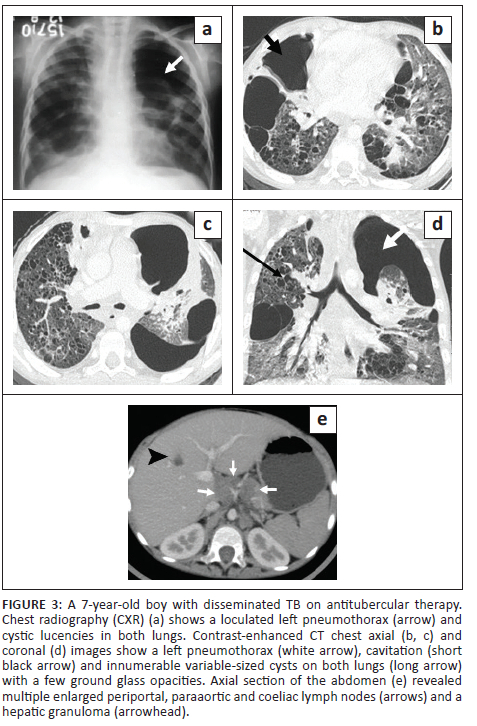

A 7-year-old boy, previously diagnosed with disseminated TB, on ATT for 3 months and on home oxygen therapy, presented to the paediatric outpatient department with complaints of intermittent increased cough from before and was found to have decreased oxygen saturation on room air. He underwent a CXR (Figure 3) that revealed a left loculated pneumothorax. The patient was admitted for assessment of multidrug resistant (MDR) TB and air leak. Contrast-enhanced CT chest (Figure 3) confirmed the left pneumothorax and revealed a thick-walled cavity in the right middle lobe and multiple cysts in both lungs. A previous CECT chest 2 months prior (Figure 4) was reviewed and revealed GGOs, a few tiny cysts, multiple bilateral nodules, along with necrotic mediastinal and abdominal lymphadenopathy, and a few small hypodense lesions in the liver suggestive of non-calcified granulomas. There was an interval increase in the number and size of the lung cysts, with a decrease in the number of nodules. Sputum microscopy and culture were negative. Bronchoscopy indicated signs of chronic inflammation and destruction of the distal bronchial segments and provided abnormal early entry into numerous cavitary structures, unlike the non-diseased areas where the distal branches gradually became smaller in size and did not allow entry into the lung parenchyma. Bronchial washings sent for culture were positive for TB (rifampicin sensitive). The patient was continued on ATT and demonstrated subsequent improvement.

Most patients with tuberculosis who develop lung cysts have extensive bilateral infiltrative and exudative disease as a result of the pneumonic process.1,4,7 All the described cases had disseminated TB (with involvement of two or more noncontiguous sites), along with diffuse, bilateral lung involvement. These cystic lung lesions are often associated with centrilobular nodules and branching opacities in surrounding areas.2,3,6 Antibiotics were administered in all five cases, and none showed superadded bacterial infection. Three cases revealed numerous nodules, GGOs and consolidations. In Case 2, two CT studies were performed 2 months apart, which demonstrated a reduction in the lung nodules on treatment, with a corresponding increase in the number of cysts. Two cases showed predominantly cystic changes, with only a few nodules. One of these (Case 5) had received 5 months of ATT for MDR TB. In the presented cases, the cystic lesions developed during isoniazid treatment, rather than before or after treatment. This is in contrast to previous literature that describes certain instances of patients developing cystic lung lesions after isoniazid treatment.7

Tuberculous cysts are prone to rupture, leading to the development of recurrent pneumothoraces or pneumomediastinum.1,2,7,9 Pneumothorax was seen in four of the cases, likely as a result of cyst rupture. However, in Case 1, both cyst rupture and additional mechanical ventilation possibly played a role in the development of pulmonary interstitial emphysema and pneumomediastinum, which is difficult to differentiate radiologically.